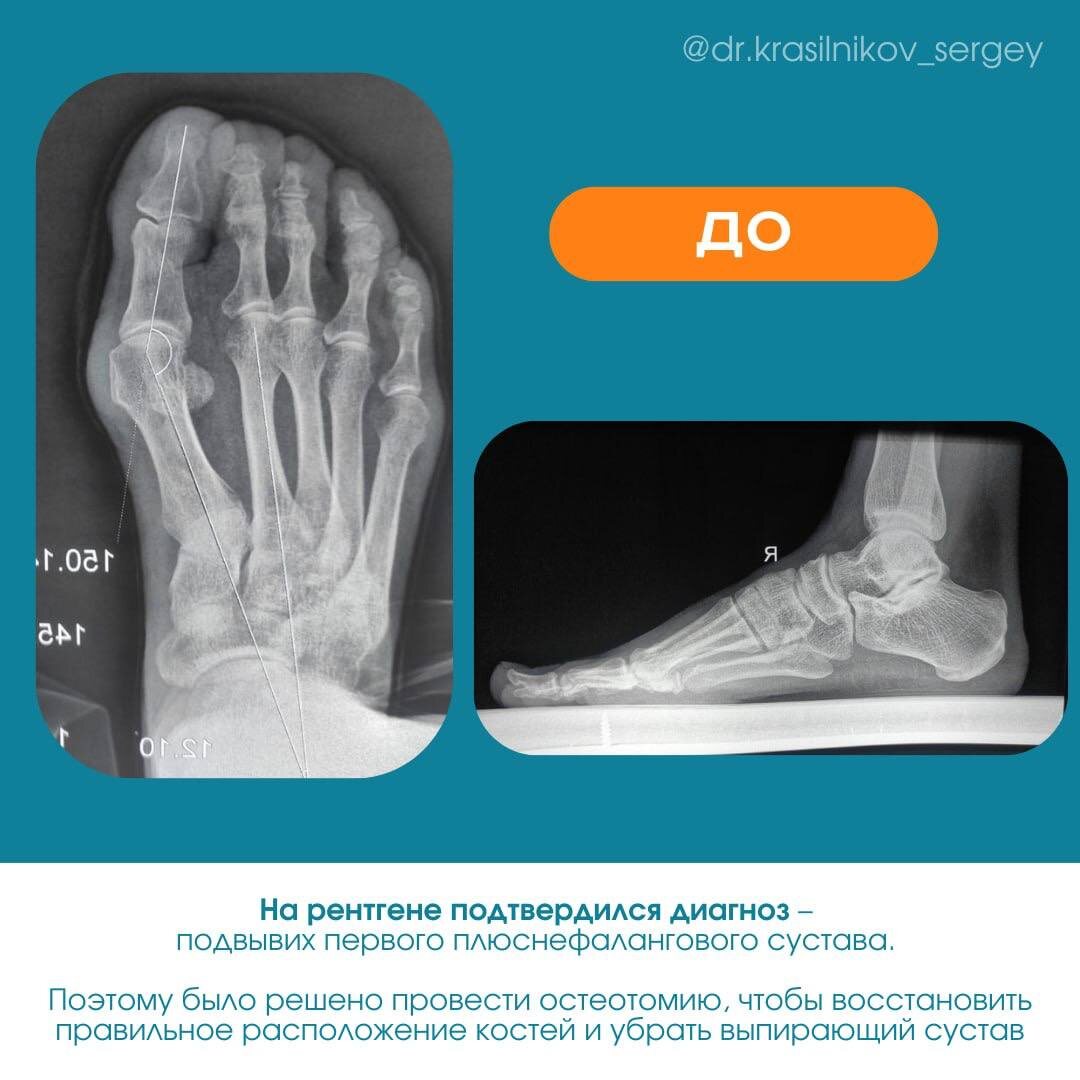

После осмотра и рентгена было решено провести остеотомию первой плюсневой кости. Подготовительные процедуры (такие как сбор анализов и медицинский педикюр) прошли быстро и вот, повязка на месте.

Для консультации понадобится рентген стоп в двух проекциях: прямой и боковой под нагрузкой (стоя).